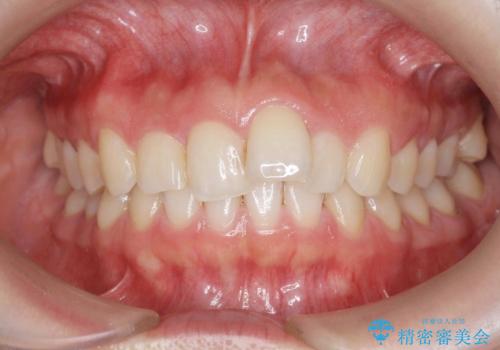

八重歯を矯正治療で治したい!

出っ歯に見える前歯の改善 部分ワイヤーとマウスピース矯正

担当医 大元洋佑